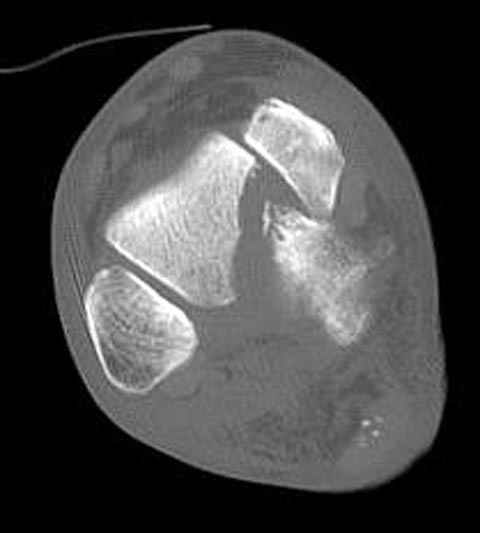

Уважаемые участники русского Ортофорума, поздравляю всех со всеми прошедшими праздниками: Новым годом, Рождеством, Hanukkah, Kwanzaa, желаю участникам всего наилучшего и здоровья.Повреждение таранной кости.Больной 81г автоавария, повреждение таранной кости, здесь снимки. Какие рекомендации?Djoldas Kuldjanov, MDDepartment of Orthopedic SurgerySt. Louis University Medical Center

В декабре у меня был пациент с политравмой и аналогичным повреждением тарана с подвывихом в таранно- ладьевидном суставе, единственное отличие - отломок головки тарана был меньше по размеру и фрагментирован, поэтому его фиксация была невозможна.

Для доступа к задне-медиальному суставному фрагменту я выполнил косую остеотомию внутренней лодыжки у её основания -получается хороший доступ к голеностопу, адекватный обзор и возможность восстановить суставную поверхность. фрагмент фиксировал двумя 3,5 мм спонгиозными винтами с неполной резьбой, *утопив* головки винтов в кость. Аналогичная фиксация и двумя тягловыми винтами и внутренней лодыжки. \в качестве альтернативы для

фиксации фрагмента тарана можно было бы использовать и герберт винты, но по организационным причинам :-(( набора не оказалось под рукой).

Повторный осмотр назначил через 2 мес с момента операции. Отдаленных наблюдений такого подхода у меня нет( достаточно редкий тип повреждений таранаHawkins II), но наблюдения в ближайшем послеоперационном периоде выглядели вполне прилично, на мой взгляд.

Вдогонку по поводу перелома таранной кости, больная 81, не страдает диабетом, перелом закрытый, в первый же день поступления ограничились временным наружным фиксатором (как на снимке).

Примеры на снимке...